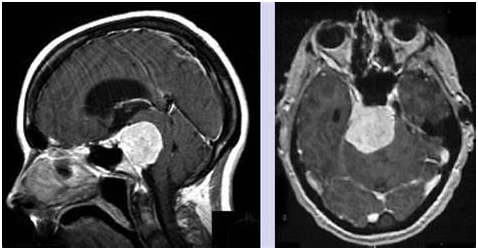

岩斜区脑膜瘤是发生于上三分之二的斜坡,硬脑膜附着在岩斜交界处。它们位于内听道的内侧,加塞神经节的后方。这将它们与发生在斜坡中线附近的斜坡脑膜瘤区分开来。岩斜病变在脑干后方及两侧均有分布,在临床表现前可累及海绵窦、岩斜窦、中颅窝、鞍旁区、幕区、枕骨大孔、梅克尔腔及/或其他各种颅神经孔。此外,它们还可能移位或包围该区域的脑血管结构,并可能通过硬脑膜侵入和/或渗入下位骨。这些病变的自然史表现为进行性生长和脑干受压,较终导致神经功能下降和不可避免的死亡。

尽管现代外科技术和多种治疗手段不断发展,岩斜区脑膜瘤的治疗仍面临挑战。在我们对这些肿瘤的治疗中,存在四个主要变量影响这些患者的治疗选择:(1)脑干症状的存在或不存在,(2)海绵窦受累,(3)患者的年龄,(4)肿瘤和脑干之间是否存在蛛网膜下腔。如果可行,对有症状的病人,无论大小,更佳治疗仍然是全切除。然而,功能结果和生活质量也需考虑,放疗已被证明是一个合适的术后辅助治疗。因此,对于有海绵窦受累患者,在辅助放射外科治疗的同时,计划通过减压和从放射敏感结构中切除肿瘤来达到良好的功能效果。当肿瘤损害了蛛网膜下腔并附着在脑干上时,我们也使用这种策略。无症状肿瘤是有争议的,因为生长速度是可变的,很难评估。如果肿瘤一直生长并引起症状,我们建议手术。